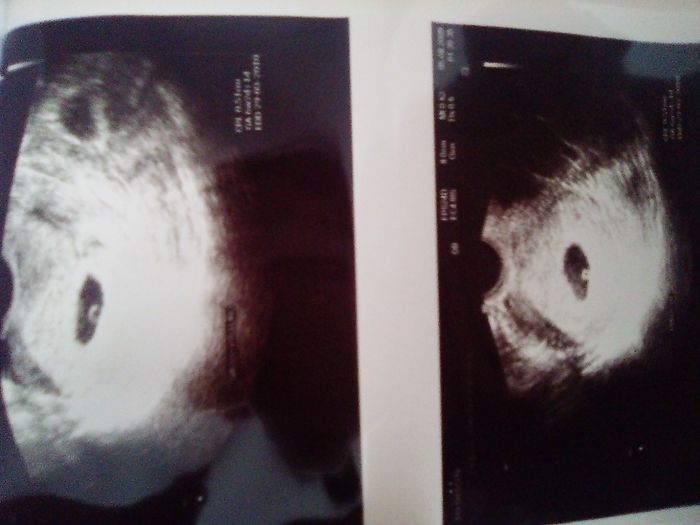

Ciao ragazze, Oggi ho fatto la traslucenza nucale e la dottoressa mi ha detto che il fagiolino era in posizione impeccabile,tanto che il tubercolo si vedeva benissimo e mi ha detto femmina al 100%. Io già da ramzi avevo predetto femmina, ma aspettavo...